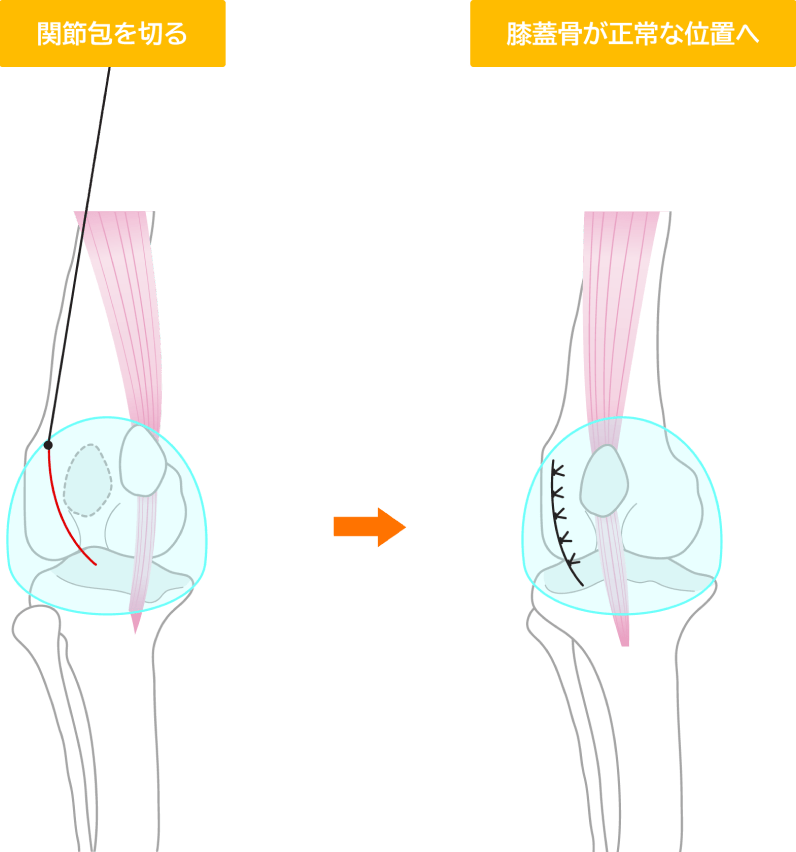

外側支帯縫縮術

膝関節を包む組織(関節包)を調整します。内側に脱臼する場合は外側を、外側に脱臼する場合は内側を縫い縮めることで、膝蓋骨を正常な位置に引き戻します。